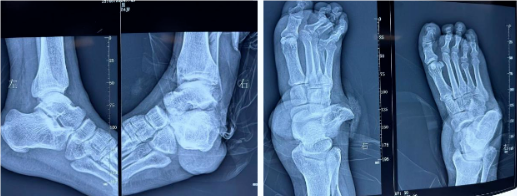

“伤者8处骨折合并9个关节脱位,开放性伤口可见肌腱断裂,足部供血系统近乎崩溃。这类多发性高能量创伤往往伴随截肢甚至死亡风险。”接诊医生回忆时仍心有余悸。医学影像显示:右胫腓骨开放性粉碎性骨折;右足多发性开放性骨折伴脱位(距骨骨折、骰骨骨折、跟骨骨折、跟距关节脱位、距舟关节脱位、跟骰关节脱位、右足1-3趾远节趾间关节及跖趾关节脱位);左胫腓骨闭合性骨折;左外踝撕脱骨折。